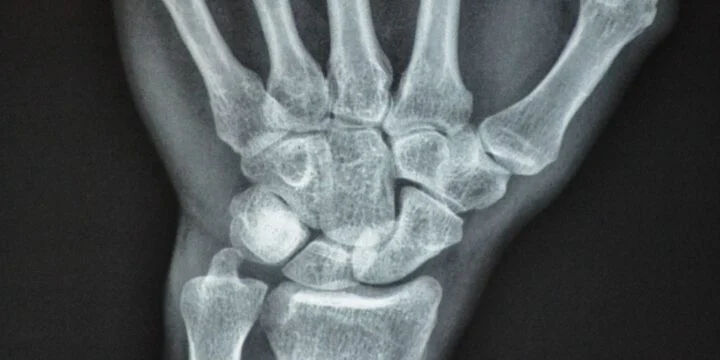

German physicist Wilhelm Conrad Röntgen discovered x-rays.

OTD in 1895: German physicist Wilhelm Conrad Röntgen discovered x-rays.

On this day, Röntgen produced and discovered electromagnetic radiation in the wavelength called Röntgen rays, which we know today as x-rays. Röntgen won a Nobel Prize in 1901 for this discovery.

World Radiography Day

On this day in 1895, x-rays were discovered, and the world of medicine has been all the better for it since! World Radiography Day raises awareness of how essential x-rays are while promoting proper use to ensure we don’t get exposed to too much radiation!